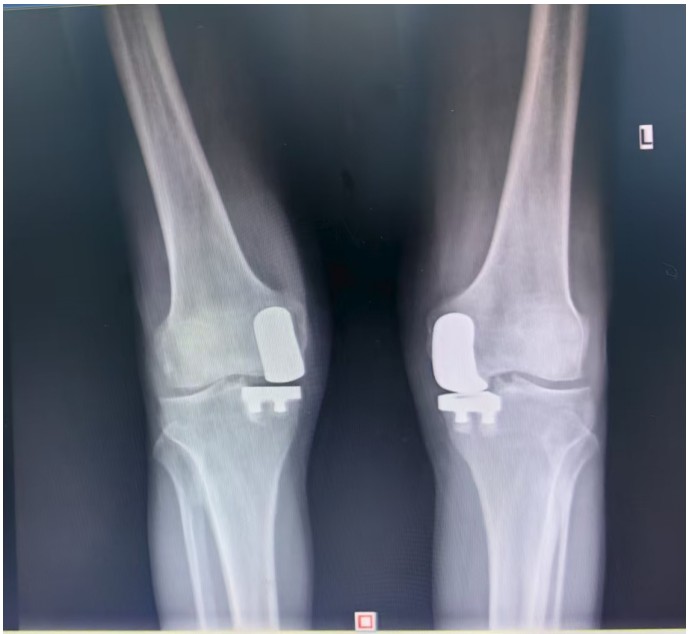

據(jù)了解,患者1年前無明顯誘因出現(xiàn)雙膝關(guān)節(jié)疼痛,以右側(cè)膝關(guān)節(jié)為主,近5個月來雙膝關(guān)節(jié)疼痛明顯加重,不但日常行走困難,生活質(zhì)量更是受到極大影響。經(jīng)多家醫(yī)院治療效果均不理想,了解到衡陽市中心醫(yī)院關(guān)節(jié)外科在關(guān)節(jié)置換領(lǐng)域擁有豐富的臨床經(jīng)驗和良好的患者口碑,毅然決定赴衡求醫(yī)。醫(yī)生發(fā)現(xiàn)患者雙膝關(guān)節(jié)已有內(nèi)翻畸形,關(guān)節(jié)內(nèi)側(cè)骨性膨大,X線提示雙膝退行性病變,雙膝內(nèi)側(cè)間隙明顯狹窄,手術(shù)為最佳治療方式。為了達(dá)到根治目的,羅湘平主任醫(yī)師、彭健副主任醫(yī)師為患者進行了詳細(xì)查體及綜合評估,術(shù)前組織開展多學(xué)科討論(MDT)。考慮到易叔叔的膝關(guān)節(jié)骨關(guān)節(jié)炎僅局限于內(nèi)側(cè),外側(cè)間室軟骨良好,若采用全膝關(guān)節(jié)置換術(shù)會將失去正常關(guān)節(jié)間室的軟骨與韌帶,創(chuàng)傷較大,便為其制定了右膝關(guān)節(jié)單髁置換手術(shù)治療方案。在充分完善術(shù)前準(zhǔn)備后,羅湘平主任、彭健副主任醫(yī)師團隊為患者實施了右側(cè)膝關(guān)節(jié)單髁置換術(shù)。手術(shù)過程順利,團隊?wèi)?yīng)用微創(chuàng)術(shù)式(MIS)及“精準(zhǔn)間隙平衡技術(shù)”,最大程度減少了手術(shù)創(chuàng)傷,為術(shù)后快速康復(fù)奠定了堅實基礎(chǔ),術(shù)后第二天即可借助助行器下地活動。6天后團隊順利為患者實施了左側(cè)膝關(guān)節(jié)單髁置換手術(shù)。目前,易叔叔在關(guān)節(jié)外科醫(yī)護團隊的精心指導(dǎo)和康復(fù)治療下,恢復(fù)情況良好,雙側(cè)膝關(guān)節(jié)活動度輕松達(dá)到90°,膝關(guān)節(jié)功能顯著改善,能夠獨立下地行走,對手術(shù)效果非常滿意,已于9月10日順利出院。

羅湘平主任介紹,膝單髁置換術(shù)是針對膝關(guān)節(jié)單側(cè)間室病變的微創(chuàng)手術(shù),該術(shù)式通過置換單側(cè)股骨或脛骨受損軟骨表面,保留交叉韌帶及正常骨質(zhì)結(jié)構(gòu),因創(chuàng)傷小、恢復(fù)快被稱為膝關(guān)節(jié)置換中的“補牙”技術(shù),適用于單間室骨關(guān)節(jié)炎且韌帶功能完整的患者。膝關(guān)節(jié)單髁置換為特定的膝關(guān)節(jié)疾病患者提供了一種較為理想的治療選擇,它以較小的手術(shù)創(chuàng)傷、良好的術(shù)后功能恢復(fù)效果,幫助患者緩解疼痛,恢復(fù)正常的生活和活動能力。